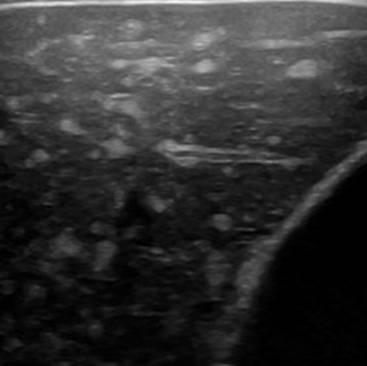

Hamartoma đường mật

» Thông tin: Nam giới – 39 tuổi.

» Lâm sàng: Kiểm tra sức khỏe.